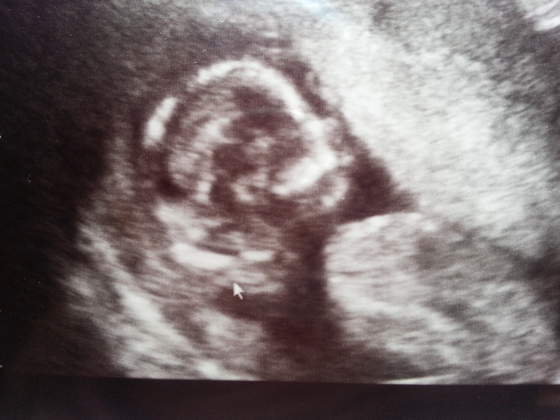

No fotka kozaktak 3dnajbardziej opłaca się 3d później bo teraz to ludzik wygląda jak "obcy"

ja miałam po prostu to szczęście, że na genetycznym miałam taki aparat co 3d zrobił i lekarza, który mnie zna od podstawówki i jak mu mówiłam, że ma wypatrzeć dziewczynkę.. to milczał i na koniec zatrzymał w momencie, gdzie widać ptaszka długości nosa

i powiedział, że na 70%chłopak. Mój prawiemąż dumny z długości ptaszka młodego a ja się modlę o te 30% (zawsze bardzo chciałam mieć dziewczynkę) no i ciotka mnie pocieszyła, że może "to duża broszka po prostu"

Zor na prenataln 12 tydz. Widzialam narzady wszystko na zewnatrz jeszcze bylo ale sprawne oko doktora wyliczylo kat nachylenia narzafow do cialka i mowi ze dxiewuszka moze dzis potwierdzichcialabym synka ale z corci tez bede happy